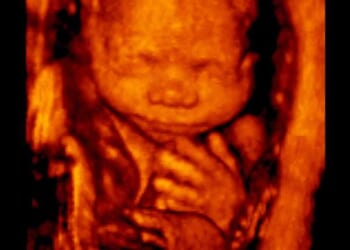

10 Top Reasons You Should Choose A Pro-Life OB-GYN